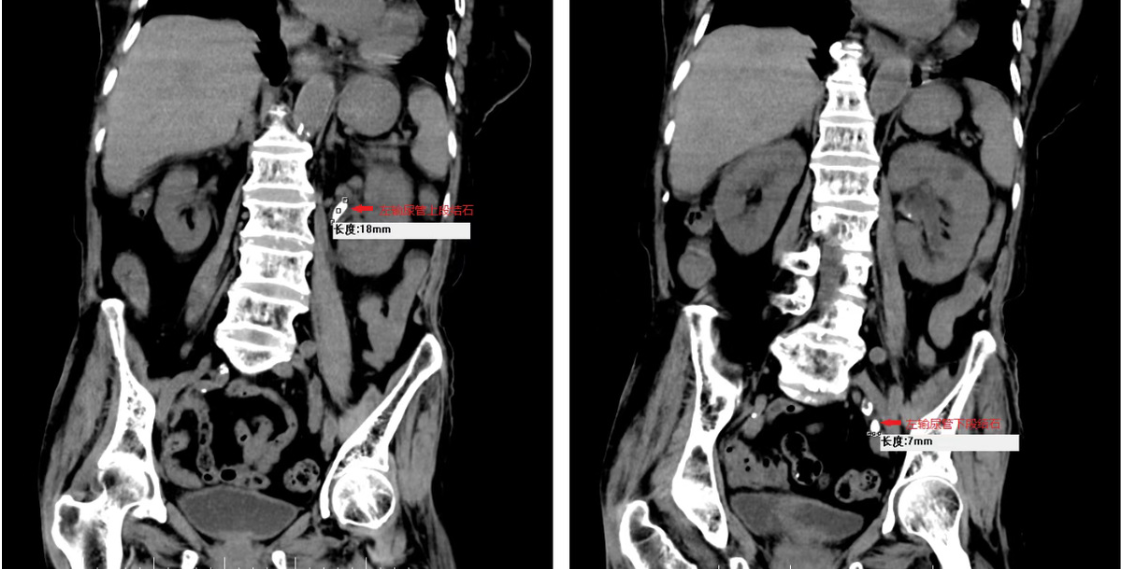

影像检查显示患者左输尿管上下段多发结石,脓性分泌物已形成压力性喷涌。医疗团队面临两难抉择:传统取石术对高龄多脏器衰竭患者风险极高,而持续感染将加速多器官功能崩溃。泌尿外科果断采取"经尿道左输尿管支架置入术",通过微创技术建立脓液引流通道,成功实现肾盂压力梯度释放。

手术中可见乳白色脓液自输尿管开口喷射,证实术前感染判断。术后三维重建显示支架精准跨越结石梗阻区,上端锚定肾盂,下端固定膀胱,有效构建泌尿系"生命通道"。该应急方案为后续抗感染治疗赢得关键时间窗,但下段结石因密度过高仍未显影,预示二期治疗仍存挑战。